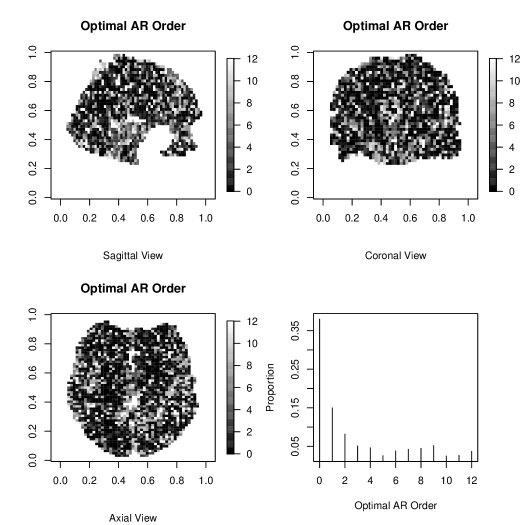

Figure 7 presents the distribution of optimal AR orders estimated from SVARO across voxels. The most frequent order is the zero order, or no autocorrelation in the time series, accounting for approximately 35% of the voxels. Interestingly, the next highest is order 8, with 9.4% of the voxels. Overall, roughly 51% of the voxels exhibit an AR order greater than 3. The existence of these higher orders and the variability in the orders is in general agreement with our exploratory analysis of the face repetition data set (see Section 1.1) and indicates the necessity of our proposed model.